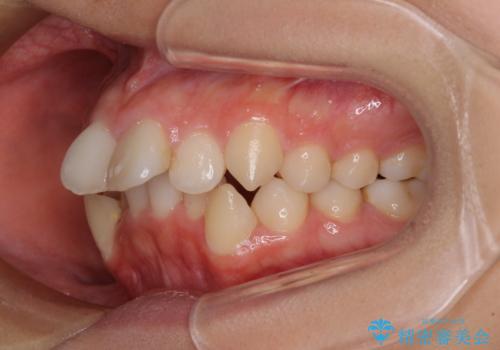

- 咬み合わせと、前歯のデコボコや八重歯、飛び出した口元を気にして来院された患者様です。

上顎は歯列不正が強く、右側臼歯部の咬み合わせは歯1本分ずれている状態でした。